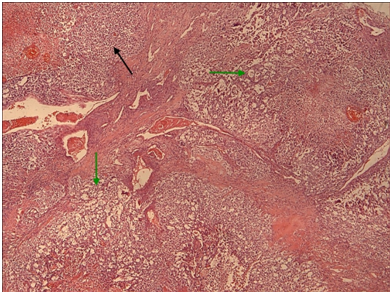

Figure 5 Mediastinal seminoma, like its gonadal counterpart, shows islands (green arrows) of large tumor cells with optically clear cytoplasm (due to large amounts of stored glycogen). These islands are separated by fibrous septa (black arrows) heavily infiltrated by non-neoplastic lymphocytes. (H + Ex10).

Figure 9 Yolk sac the microcystic / macrocystic reticular pattern of growth (green arrows) is the most common finding in yolk sac tumors (>70% of cases).Nevertheless, it is possible to encounter more solid areas (black arrow). (H+E,x4).